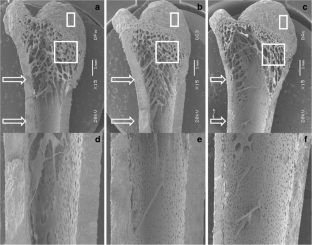

This study evaluates the effect of three calcium levels in the diet (normal, moderate, and severe calcium depletion) on bone metabolism of male Wistar rats during their growth period. Bone mineral density (BMD) and femur length were determined in vivo during the growth stage using a single X-ray transmission system. The apparent calcium absorption was calculated in the rat adolescent and adulthood stages. At the end of the experiment, calcium concentrations in serum and urine were analyzed. The bones were evaluated postmortem to corroborate in vivo analyses. Microstructural properties of cortical and trabecular tissues of femurs bones were assessed using scanning electron microscopy. Bone mineral contents (Mg, Ca, P, and K) were quantified by inductively coupled plasma. Severe calcium depletion in the diets in the development stage affects the bone quality parameters such as bone mineral density and mineral content. Moreover, it was found thinner cortical and trabecular bone areas. Additionally, it was found that severe calcium depletion increased the apparent absorption of calcium as a defense mechanism, but with the decrease of the BMD peak, and the thickness of cortical bone as well as trabecular bone porosity. The severe calcium depletion increased the efficiency of apparent absorption calcium as a defense mechanism, but, even so, decreases the BMD peak as well as the thickness of cortical bone and trabecular bone porosity.

Fig. 4